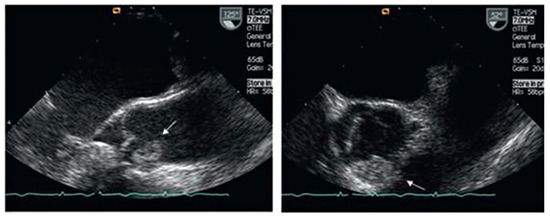

A patient with Morbus Behçet was admitted with severe symptomatic aortic regurgitation caused by aortitis that mimicked infective endocarditis. After aortic valve replacement and antibiotic treatment, regurgitation and systemic inflammation recurred....